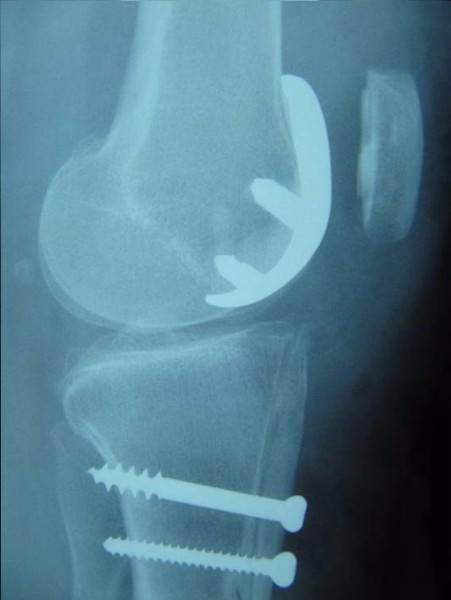

Dans le cadre d'une arthrose isolée de la rotule et de la trochlée fémorale, on peut envisager une Prothèse Fémoro-Patellaire.